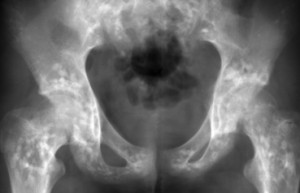

Патология проявляется в виде множества уплотнений, которые обычно располагаются симметрично. Для точного понимания проблемы необходимо изучить рентгеновский снимок. Это заболевание встречается крайне редко, зарегистрировано всего около 100 случаев. Оно является врожденным. Уплотнения в костях имеют овальную форму и могут достигать размеров от 2 до 10 мм.

Каждая форма имеет свои уникальные характеристики. На рентгенограмме внешний вид костей изменяется: они становятся крапчатыми с множеством мелких уплотнений на округлых участках. По особенностям рисунка можно различить пятнистую и полосатую остеопойкилию. В первом случае формируются овальные уплотнения, во втором — продолговатые. Изменение формы очагов поражения указывает на прогрессирование заболевания. При смешанной форме на рентгенограмме видны уплотнения различных размеров и форм, однако такая форма встречается крайне редко.

Выявить поражение костных тканей можно только с помощью рентгенографического исследования. На рентгеновских снимках видны изменения в структуре костей. Чаще всего остеопойкилия диагностируется во время обследования на наличие других заболеваний костной системы, таких как ревматизм, остеохондроз или деформации, вызванные травмами.

Для установления точного диагноза проводится рентгенологическое исследование, которое позволяет выявить изменения в костной структуре. Поскольку заболевание не затрагивает состав крови, лабораторные анализы нецелесообразны. Результаты анализа крови и других жидкостей организма будут в пределах нормы.

На рентгеновских снимках оцениваются форма и размеры пораженных костей. При остеопойкилии внешние изменения костных тканей отсутствуют. Уплотнения формируются внутри структуры, не влияя на контуры костей. Процесс развития тканей протекает нормально, без задержек формирования или других патологий, характерных для остеопойкилии. В редких случаях с образованием очагов поражения в костях может развиваться кожное заболевание, известное как чечевицеподобный фиброз.

Очаги поражения чаще всего локализуются в костях таза, запястьев и стоп. Также часто затрагиваются плечи, предплечья, голеностопные суставы и позвонки в некоторых отделах позвоночника (крестцовом и поясничном). Череп и ребра менее подвержены образованию патологий, а ключицы остаются совершенно непораженными.